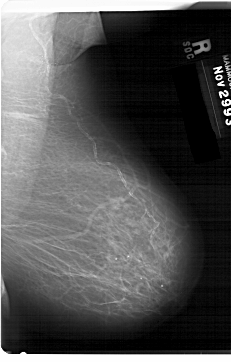

Digital Database for Screening Mammography

Volume: benign_03 Case: A-1366-1

A_1366_1.LEFT_MLO

DATE_OF_STUDY 29 11 1993

PATIENT_AGE 70

FILM_TYPE REGULAR

DENSITY 2

DIGITIZER HOWTEK 43.5

LEFT_MLO LINES 6871 PIXELS_PER_LINE 4126 BITS_PER_PIXEL 12 RESOLUTION 43.5 OVERLAY